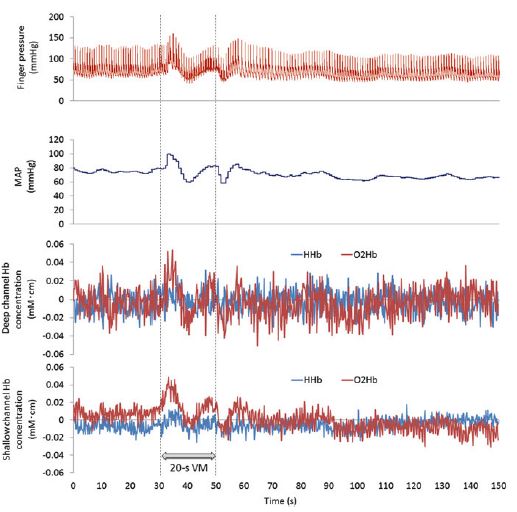

Tsubaki A, Kojima S, Furusawa AA, Onishi H.: Effect of valsalva maneuver-induced hemodynamic changes on brain near-infrared spectroscopy measurements.Adv Exp Med Biol. 2013;789:97-103